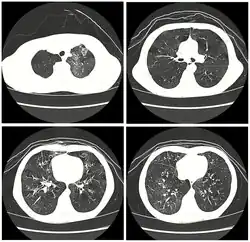

![]() | |

| High resolution CT scan showing bronchiolitis obliterans with mosaic attenuation, bronchiectasis, air trapping and bronchial thickening[3] | |

Early in the disease chest radiography is typically normal but may show hyperinflation.[6] As the disease progresses a reticular pattern with thickening of airway walls may be present.[4][6] HRCT can also show air trapping when the person being scanned breathes out completely; it can also show thickening in the airway and haziness in the lungs.[11] A common finding on HRCT is patchy areas of decreased lung density, signifying reduced vascular caliber and air trapping. This pattern is often described as a "mosaic pattern", and may indicate bronchiolitis obliterans.[6]